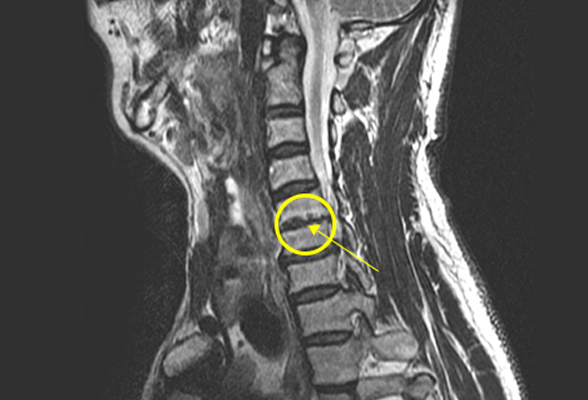

목 디스크

경추(목뼈) 사이의 디스크가 빠져나오거나 뼈 조직이

돌출되어 목으로 지나가는 척추 신경을 압박해

통증과 저린감, 근력 저하가 발생하는 질환입니다.

비수술 치료 : 약물치료, 주사치료, 물리치료, 도수치료, 신경 성형술, 수핵 성형술

수술치료 : 경추체 전방 고정술, 경추 인공디스크 치환술